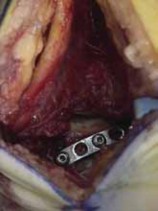

Smooth Kirschner wires are inserted, posterior to anterior, provisionally fixing the fracture.

The fracture is fixed either by interfragmentary, parallel screw fixation or a well-contoured mini-plate and interfragmentary screws.

The posterior mini-plate is contoured in a curvilinear fashion to securely buttress the posterior talus.

---

C A E

TECH FIG 4 • A. Preoperative CT image of posterior talus fracture. B. Posteromedial longitudinal incision. C. Intraoperative location of half-pins to assist in ankle and subtalar joint distraction. D. Intraoperative mini-plate fixation. E. Postoperative B D lateral view. ### TECHNIQUES